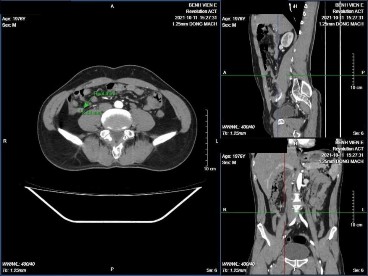

Hình 3.5: Ruột thừa tăng kích thước

BN Trần Văn D. 45 tuổi, mã bệnh án 2120430. Kết quả GPB VRT mủ. Hình ảnh phẫu thuật nội soi ruột thừa tăng kích thước, căng to, xung huyết.